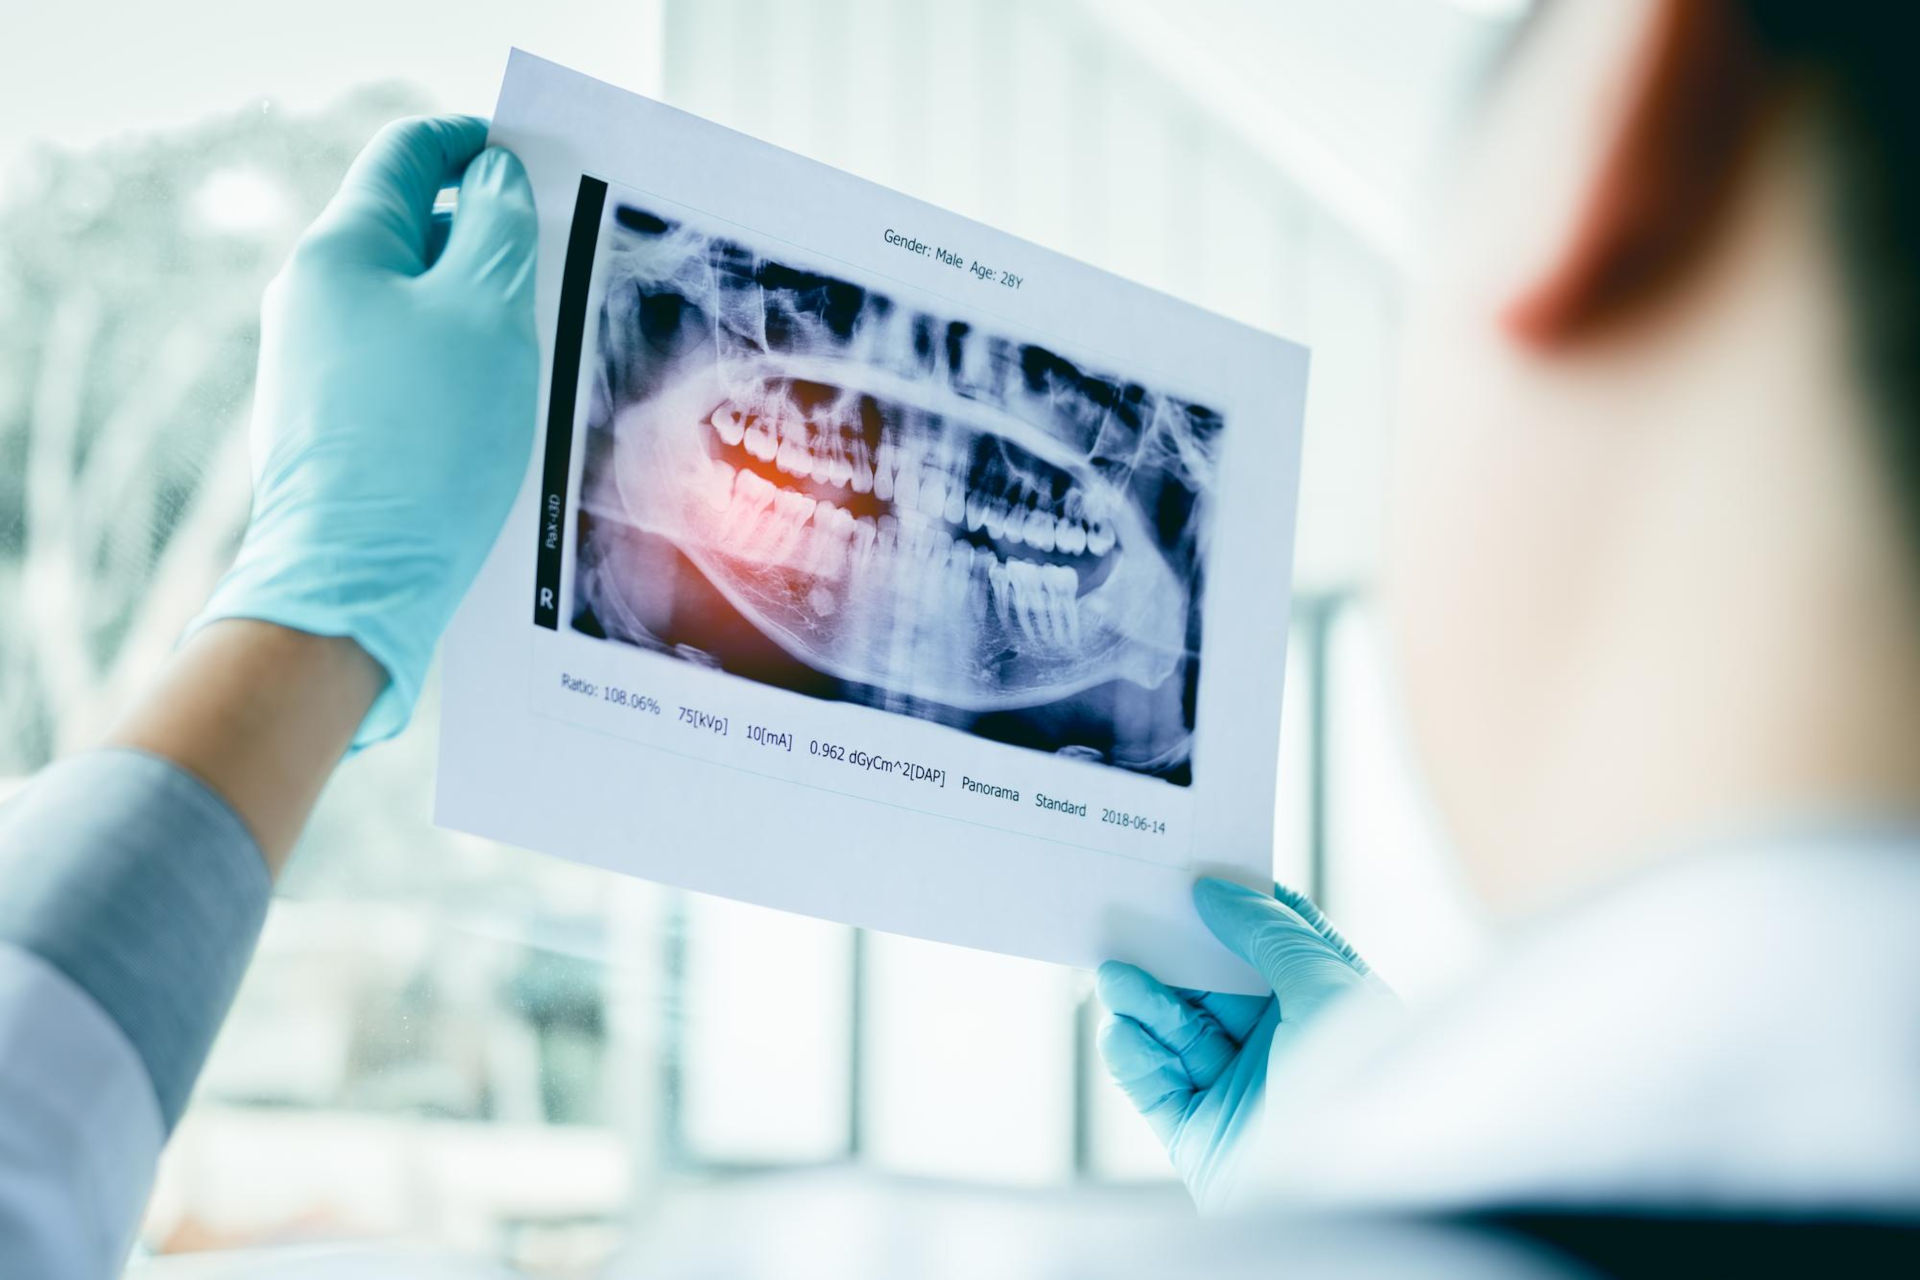

Oral surgery in dentistry is a collective term for all procedures performed by a surgeon. This includes the surgical removal of wisdom teeth or other ones that need to be extracted but are so firmly embedded that surgical intervention is necessary. The surgeon can perform bone augmentation procedures as well, that become necessary when the jaw needs to be widened or thickened, in order for an implant to be completly surrounded by bone material, for a better stability and durability.

Surgical extractions – removal of wisdom teeth

Wisdom teeth are usually firmly anchored, have 3-4 roots, and require surgical treatment to be removed. Furthermore, we often find that wisdom teeth grow inwards, are deeply imbeded in the jawbone and their position usually deviates from the normal. The reason behind it is that the facial skeleton, especially the jaw, has become smaller over the millennia, leaving less space for the same number of teeth. It is becoming increasingly common for wisdom teeth not to form at all.

If a wisdom tooth cannot grow out completely and remains partly under the gum, it can become inflamed. Cleaning these teeth can also be complicated, which can cause additional inflammation, even under the palate. This can cause pain, tooth decay, and bad breath.

Wisdom teeth in poor positions can also have a negative effect on the denture as it puts a pressure on the teeth next to it. This can lead to misalignment or crowding on full set of teeth. In these cases, braces are recommended for correction.